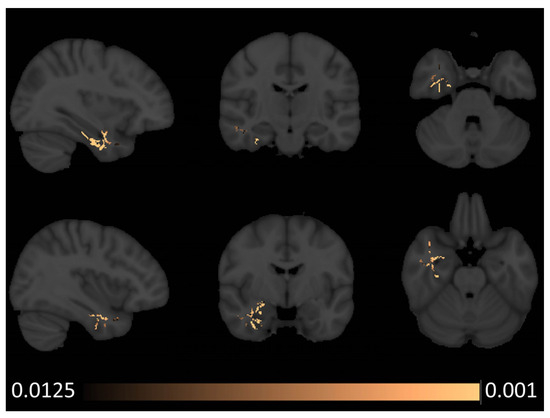

3.2. White Matter Patterns

- Radiological considerations